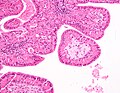

| LM | papillae with a two rows of pink (eosinophilic) epithelial cells (with cuboidal basal cells and columnar luminal cells), fibrous capsule, cystic space filled with debris, lymphoid stroma |

- Papillae (nipple-shaped structures) with a two rows of pink (eosinophilic) epithelial cells (with cuboidal basal cells and columnar luminal cells) - key feature.

- Fibrous capsule - pink & homogenous on H&E stain.

- Cystic space filled with debris in situ (not necrosis).

- Lymphoid stroma.